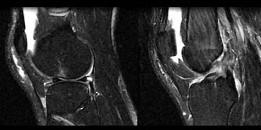

问题 男,37岁,右膝关节曾有外伤史,现感右膝关节部疼痛,请结合所提供的图像,选择最佳选项 ( )

选项 A、半月板损伤 B、后十字韧带撕裂 C、前十字韧带撕裂 D、胫骨骨折 E、未见异常

答案 C